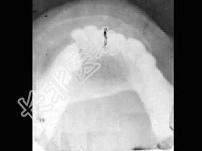

- 单项选择题女,40岁, 下颌颏部隆起,结合图像最可能诊断 ( )

A、造釉细胞瘤

B、骨软骨瘤

C、含牙囊肿

D、骨巨细胞瘤

E、动脉瘤样骨囊肿